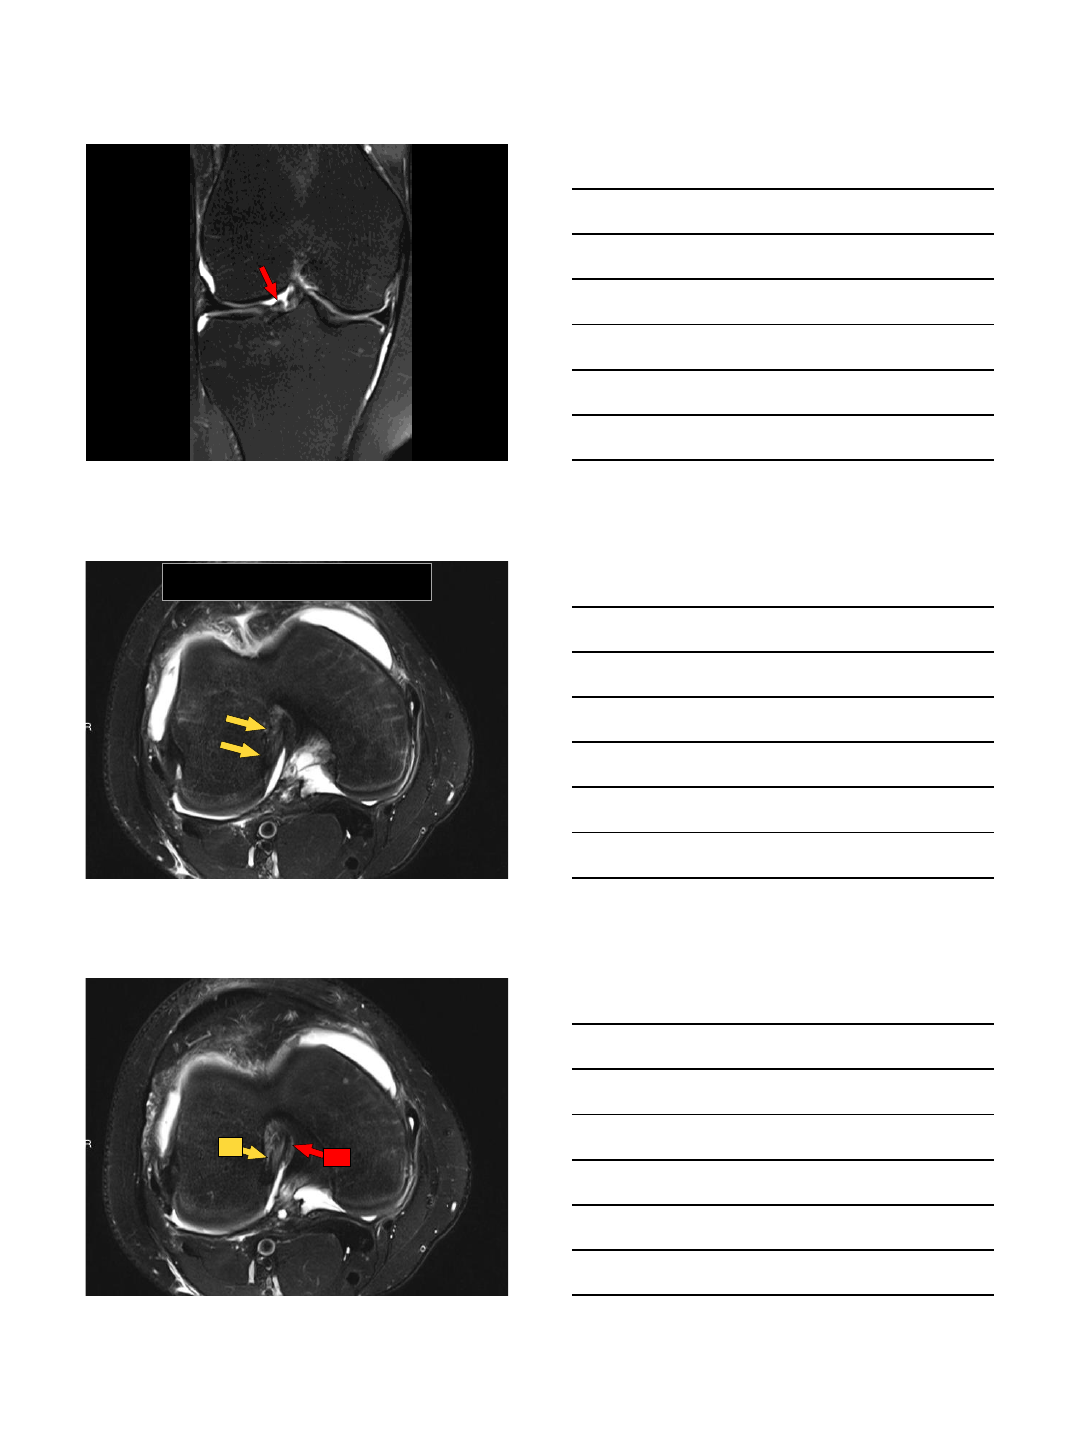

•Semilunar (C–shaped)

–Medial is more C-shaped and larger and lateral more rounded and smaller

•Divided into anterior and posterior horns and body

•Wedge shaped with biconcavity

Medial Meniscus

•Posterior horn is larger than

anterior horn

•Non-mobile –more firmly

attached to the joint capsule

•Meniscofemoral and

meniscotibial (coronary)

ligaments

Lateral Meniscus

•Anterior = Posterior Horn

•Fibers of ACL extend into anterior horn

•Posterior root attaches anterior to PCL

•Meniscofemoral ligaments –Humphrey

& Wrisberg

•Popliteomeniscal fascicles

•Fascicles (2-3)

–Meniscocapsular extension around

popliteal hiatus

–Anteroinferior: body LM to

musculotendinous portion of popliteus

–forms floor of hiatus

–Posterosuperior: post horn LM to

popliteus tendon

–forms roof of popliteal hiatus

–If ruptured, can render the LM

hypermobile; pain and locking

10/13/2015